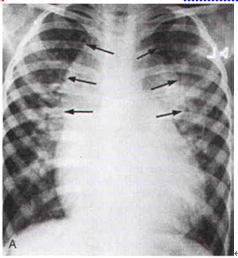

16. 3個月大男孩,主訴呼吸喘且有稍有發紺(cyanosis)現象。身體理學檢查時,發現於左上胸有一2-3度收縮噴射心雜音合併固定且寬的第二心音。其胸部X光如下,下列何者為最可能診斷?

(A)先天性肺動脈瓣膜缺乏症(congenital absence of pulmonary valve)。 (B)總肺靜脈回流異常(TAPVR)。 (C)大血管轉位合併心室中膈缺損(TGA with VSD)。 (D)雙主動脈弓(double aortic arch)。 (E)心房中膈缺損(ASD)。